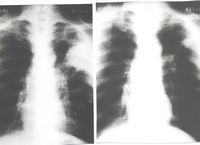

The X-ray images (from: Journal of the International Association for Biologically Closed Electric Circuits in Medicine and Biology, Vol. 1, January-December, 2002), for a 52 year old lung cancer patient show a 9.5 cm by 11 cm carcinoma (left photo), diagnosed by needle biopsy. Six platinum electrodes were inserted into the skin and into the tumor mass using X-ray monitoring. After the patient received six months of electrical treatment (EChT), the tumor completely disappeared (right photo). The patients progress has been very good.